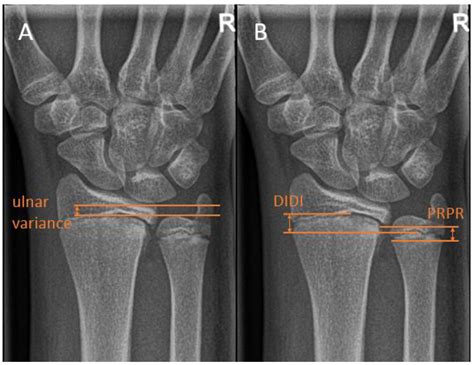

Diagnosing Positive Ulnar Variance requires more than a standard physical exam. Physicians typically rely on specific imaging techniques to accurately measure the variance. An X-ray of the wrist is the gold standard for diagnosis. However, how the X-ray is taken matters significantly.

To ensure accuracy, the patient's arm must be positioned correctly. If the arm is not properly aligned, the measurement of the ulnar variance can be falsely positive or negative. The doctor will likely request a posteroanterior (PA) view of the wrist with the forearm in a neutral position. In more complex cases, magnetic resonance imaging (MRI) may be utilized to evaluate the health of the surrounding soft tissues, such as the TFCC and the cartilage of the wrist bones, to see if damage has already occurred due to the impaction.